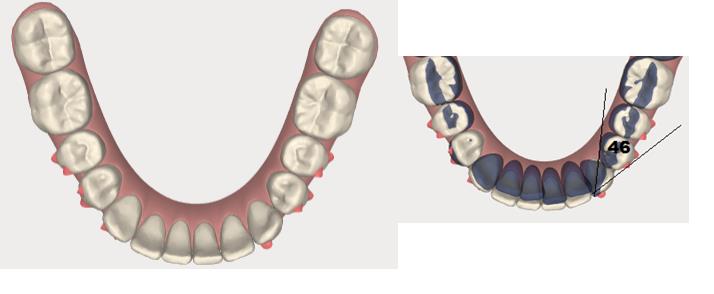

Methods: The clinical examination included extra-oral and intra-oral photographs, panoramic radiographic, lateral cephalometric, stone casts, and upper and lower arch analysis obtained from ClinCheck 3.0.The treatment planning was resolved the crowding in both upper and lower arches and the severe rotation of 33 tooth (46°) using Invisalign system as well as the canine and molar relationship, dental verticalization, adequate over jet, overbite and dental midline using the same system. The duration of the treatment was approximately eight months.

Results: In Post-treatment extra oralphotographs, no significant changes were observed at the end of the treatment. Intraoral photographs showed an important and notable improved aesthetics. The canine relationship improved slightly and molar Class Irelationship was maintained. An increase in transverse diameter was observed at the level of first premolars, second premolars and first molars. The overbite was improved. The crowding and the severe canine rotation were corrected. No obvious root resorption was radiographically evident and slight cephalometric changes.